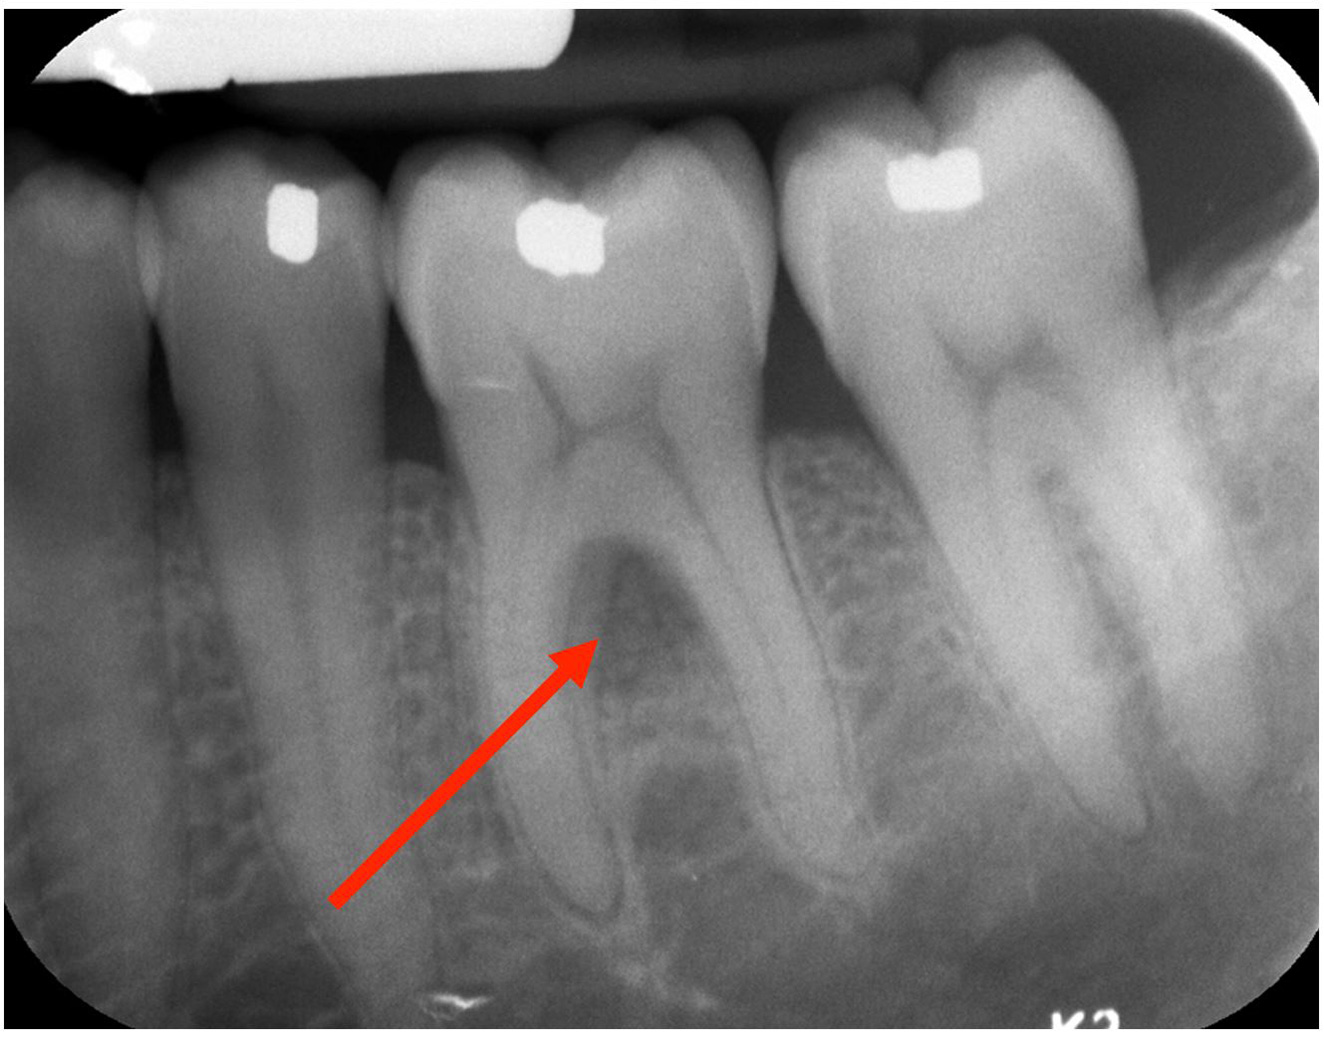

Laser Periodontal Treatment

*Follow-up x-rays 9-12 months after treatment